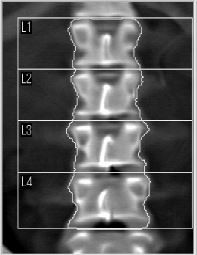

協会けんぽ 骨密度検査

40歳以上74歳までの偶数年齢の女性被保険者が対象のオプション検査となります。

骨密度検査は、骨の強さを数値で調べる検査です。

| 腰椎のみ | 1,100円 |

腰椎(腰の骨)の骨密度を測定し、骨量の状態を評価する検査です。 骨粗しょう症の早期発見に役立ちます。 |

年齢を重ねると、腰椎は次のような変化の影響で、実際より骨密度が高く測定されることがあります。

当院では、より正確な評価のため 「腰椎+股関節」を標準としてご案内しております。 |

骨密度測定画像

![]() 腰椎画像 |